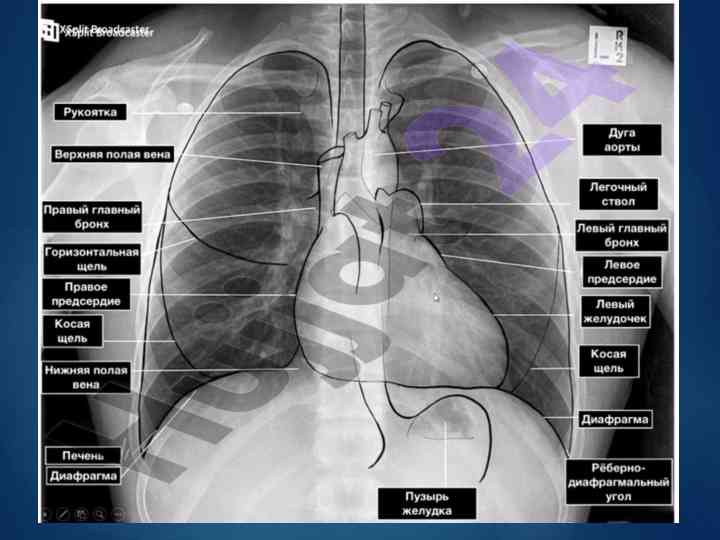

Кардиомегалия ва юрак шовкинлари таҳлили

Кардиомегалия симптоми ва унинг асосий касалликлари, шунингдек, юрак шовкинлари ва уларнинг тактикаси бўйича таҳлил.